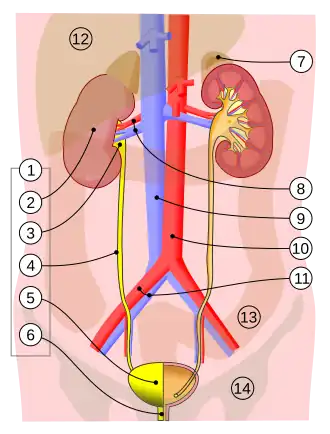

1. Мочевыделительная система человека: 2. почка 3. почечная лоханка 4. мочеточник 5. мочевой пузырь 6. мочеиспускательный канал. | |

Мочевыдели́тельная систе́ма (мочева́я систе́ма) челове́ка — система органов, формирующих, накапливающих и выделяющих мочу у человека. Состоит из пары почек, двух мочеточников, мочевого пузыря и мочеиспускательного канала. Аналогом у беспозвоночных является нефридий.